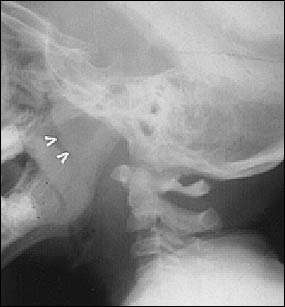

Ağzının arka üst kısmında yani burnun en arka nazofarenks denilen bölgedesinde yer alan dokulardır. Normalde bakıldığında görülmezler, görülmeleri için özel muayene yöntemi gerektirir. Geniz etleri endoskopik muayene , küçük muayene aynaları veya röntgen ile yöntemlerle görülebilir. Vücut için faydası olmayan lenf dokulardır. Genellikle çocuklarda bulunurlar. Burun etleri diye ifade edilen kavram burnun giriş kısmında bulunan ve fonksiyonu olan burun için faydalı organlardır. Genellikle geniz eti ile karıştırılır. Bunların farklı yapılar olduğu bilinmelidir.